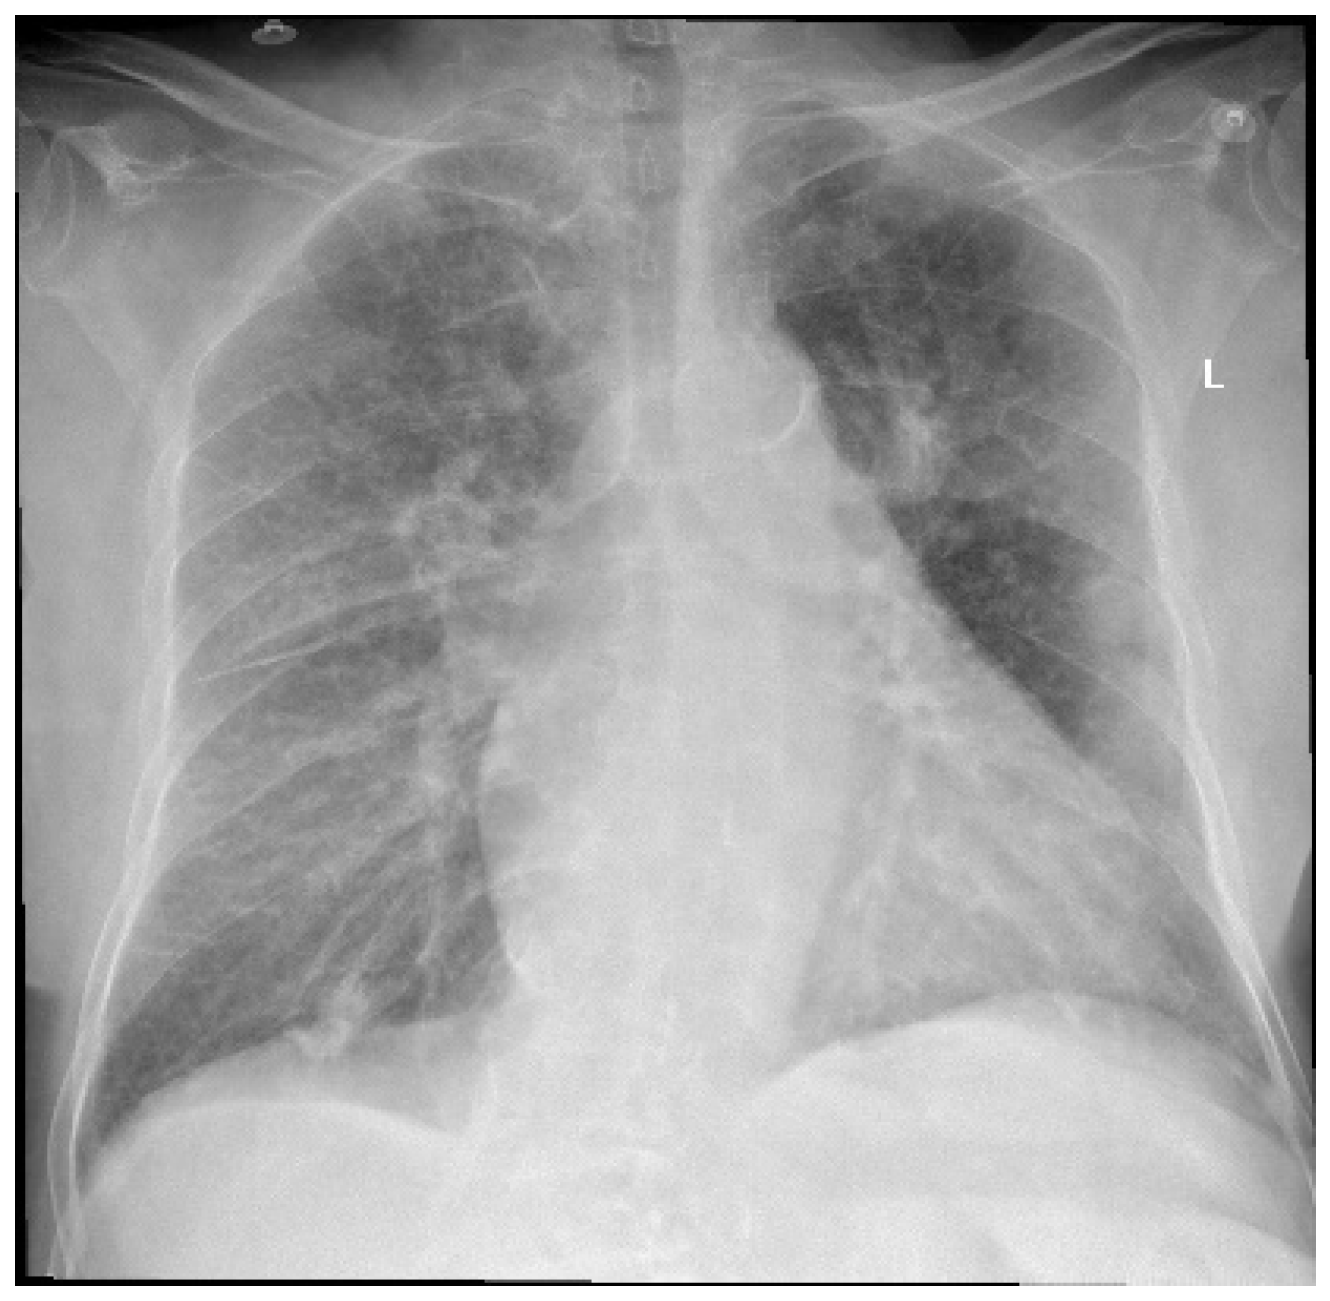

An 83-year-old female patient was admitted to the Orthopedics—Traumatology Department with a left femoral neck fracture (FNF) garden type IV due to a fall from the same height. Upon preoperative examination, the following associated comorbidities were diagnosed: bronchopneumonia (Figure 1), chronic ischemic heart disease (IHD), high blood pressure (HBP) stage 2, left ventricular failure NYHA (New York Heart Association) type 2 with a left ventricle ejection fraction (LVEF) of 50%, moderate aortic valve stenosis (mean gradient 34 mmHg, aortic valve area 10 mm), tricuspid regurgitation grade 2, and permanent atrial fibrillation (AFib), for which she was taking oral anticoagulants (rivaroxaban, 20 mg, Xarelto®, Leverkusen, Germany), diuretics (spironolactone/furosemide 50 mg/20 mg, Diurex®, Niles, IL, USA), and beta-blockers (nebivolol, 5 mg, Nebilet®, New York, NY, USA).

Figure 1.

Chest X-ray at admission—describing small left pleural effusion; bilateral diffuse reticule-micronodular interstitial lung pattern; questionable opacities at the level of the posterior left VI costal arch and right intercostal XI space; pulmonary vascular congestion; global enlarged heart; atherosclerotic aorta. L—left side.